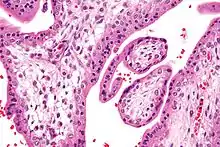

Micrograph showing chorionic villi. Intermediate magnification. H&E stain.

The bulk of the villi consist of connective tissues that contain blood vessels. Most of the cells in the connective tissue core of the villi are fibroblasts. Macrophages known as Hofbauer cells are also present.